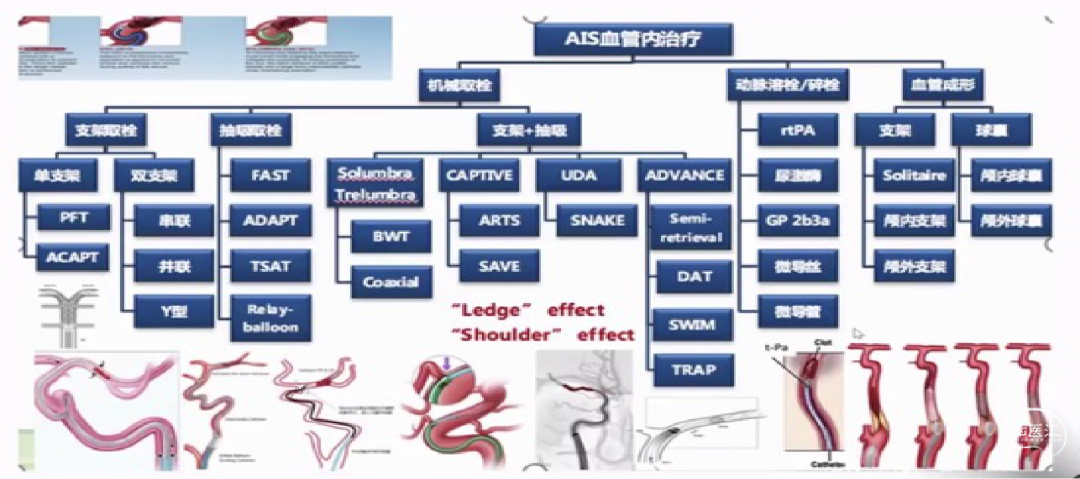

AIS血管内治疗,常用的SWIM技术中中间导管的应用不可或缺!